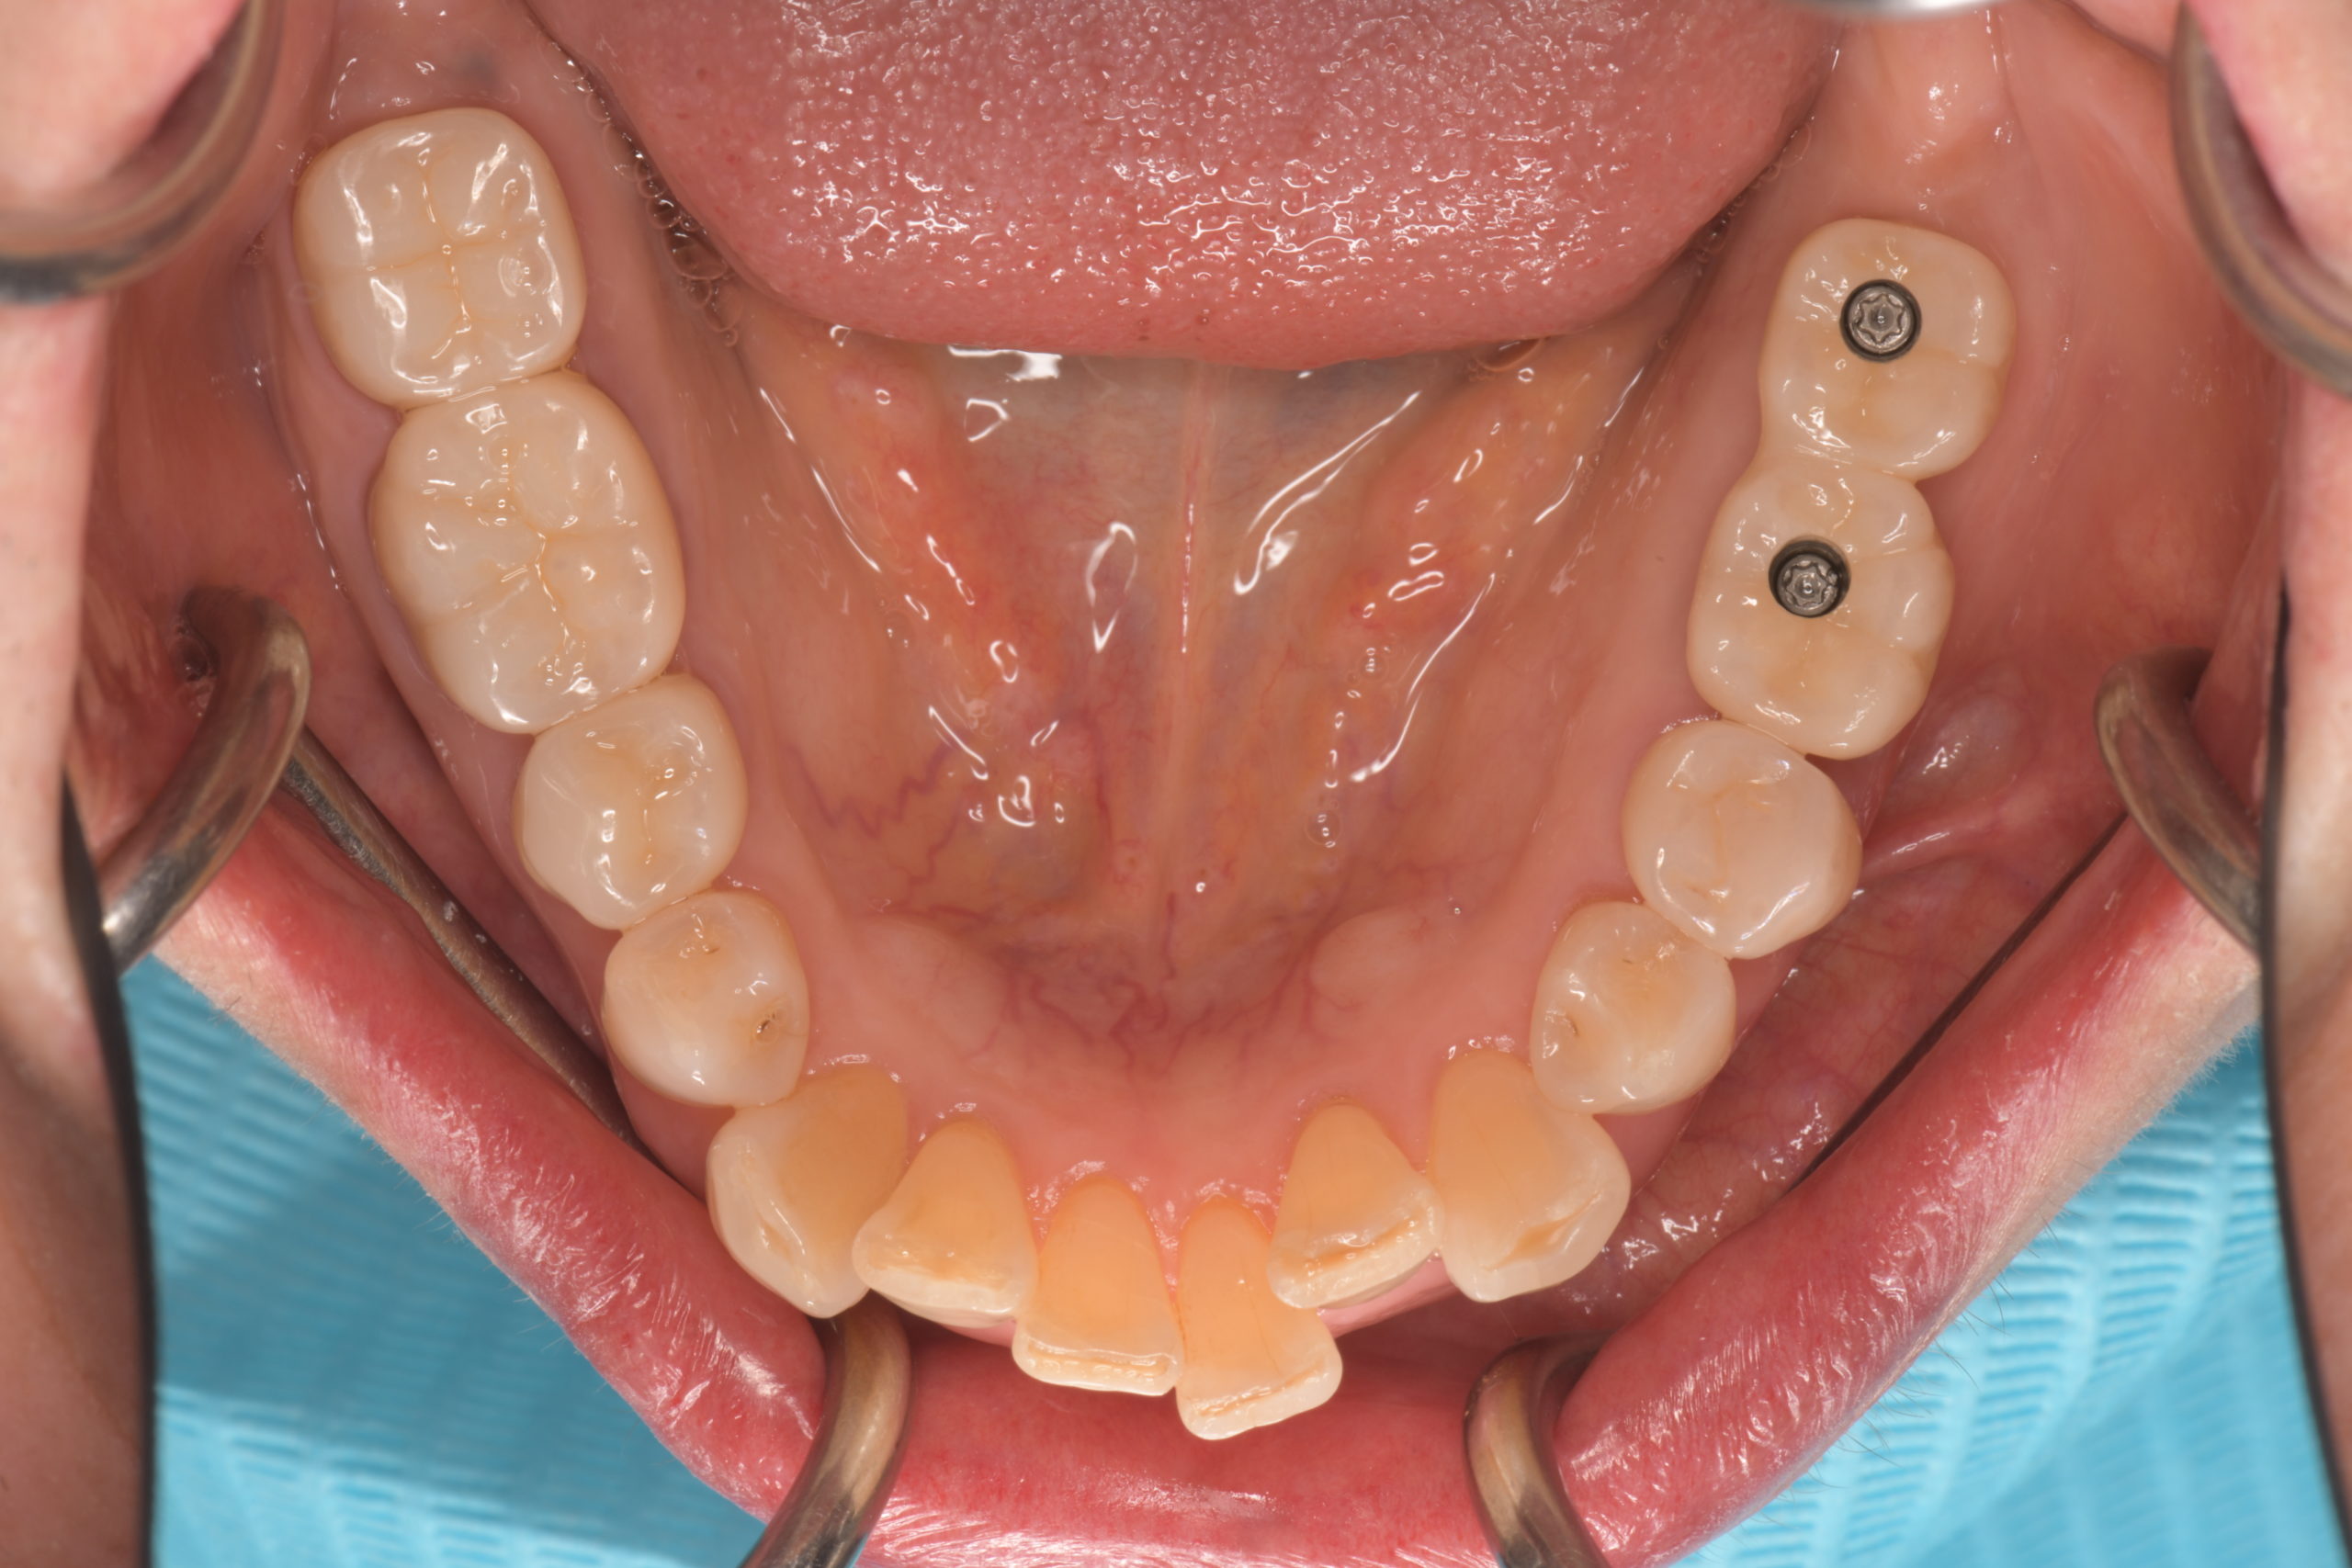

下顎臼歯部インプラント治療前

下顎臼歯部インプラント上部構造装着前

下顎インプラント治療完了

左下臼歯部インプラント治療前

左下臼歯部インプラント上部構造装着前

左下臼歯部インプラント治療完了